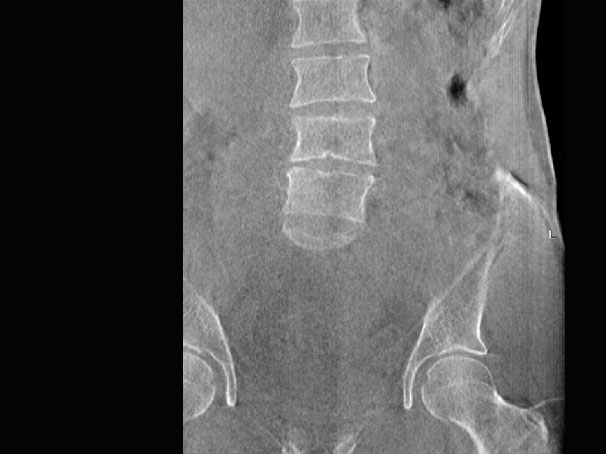

腰椎